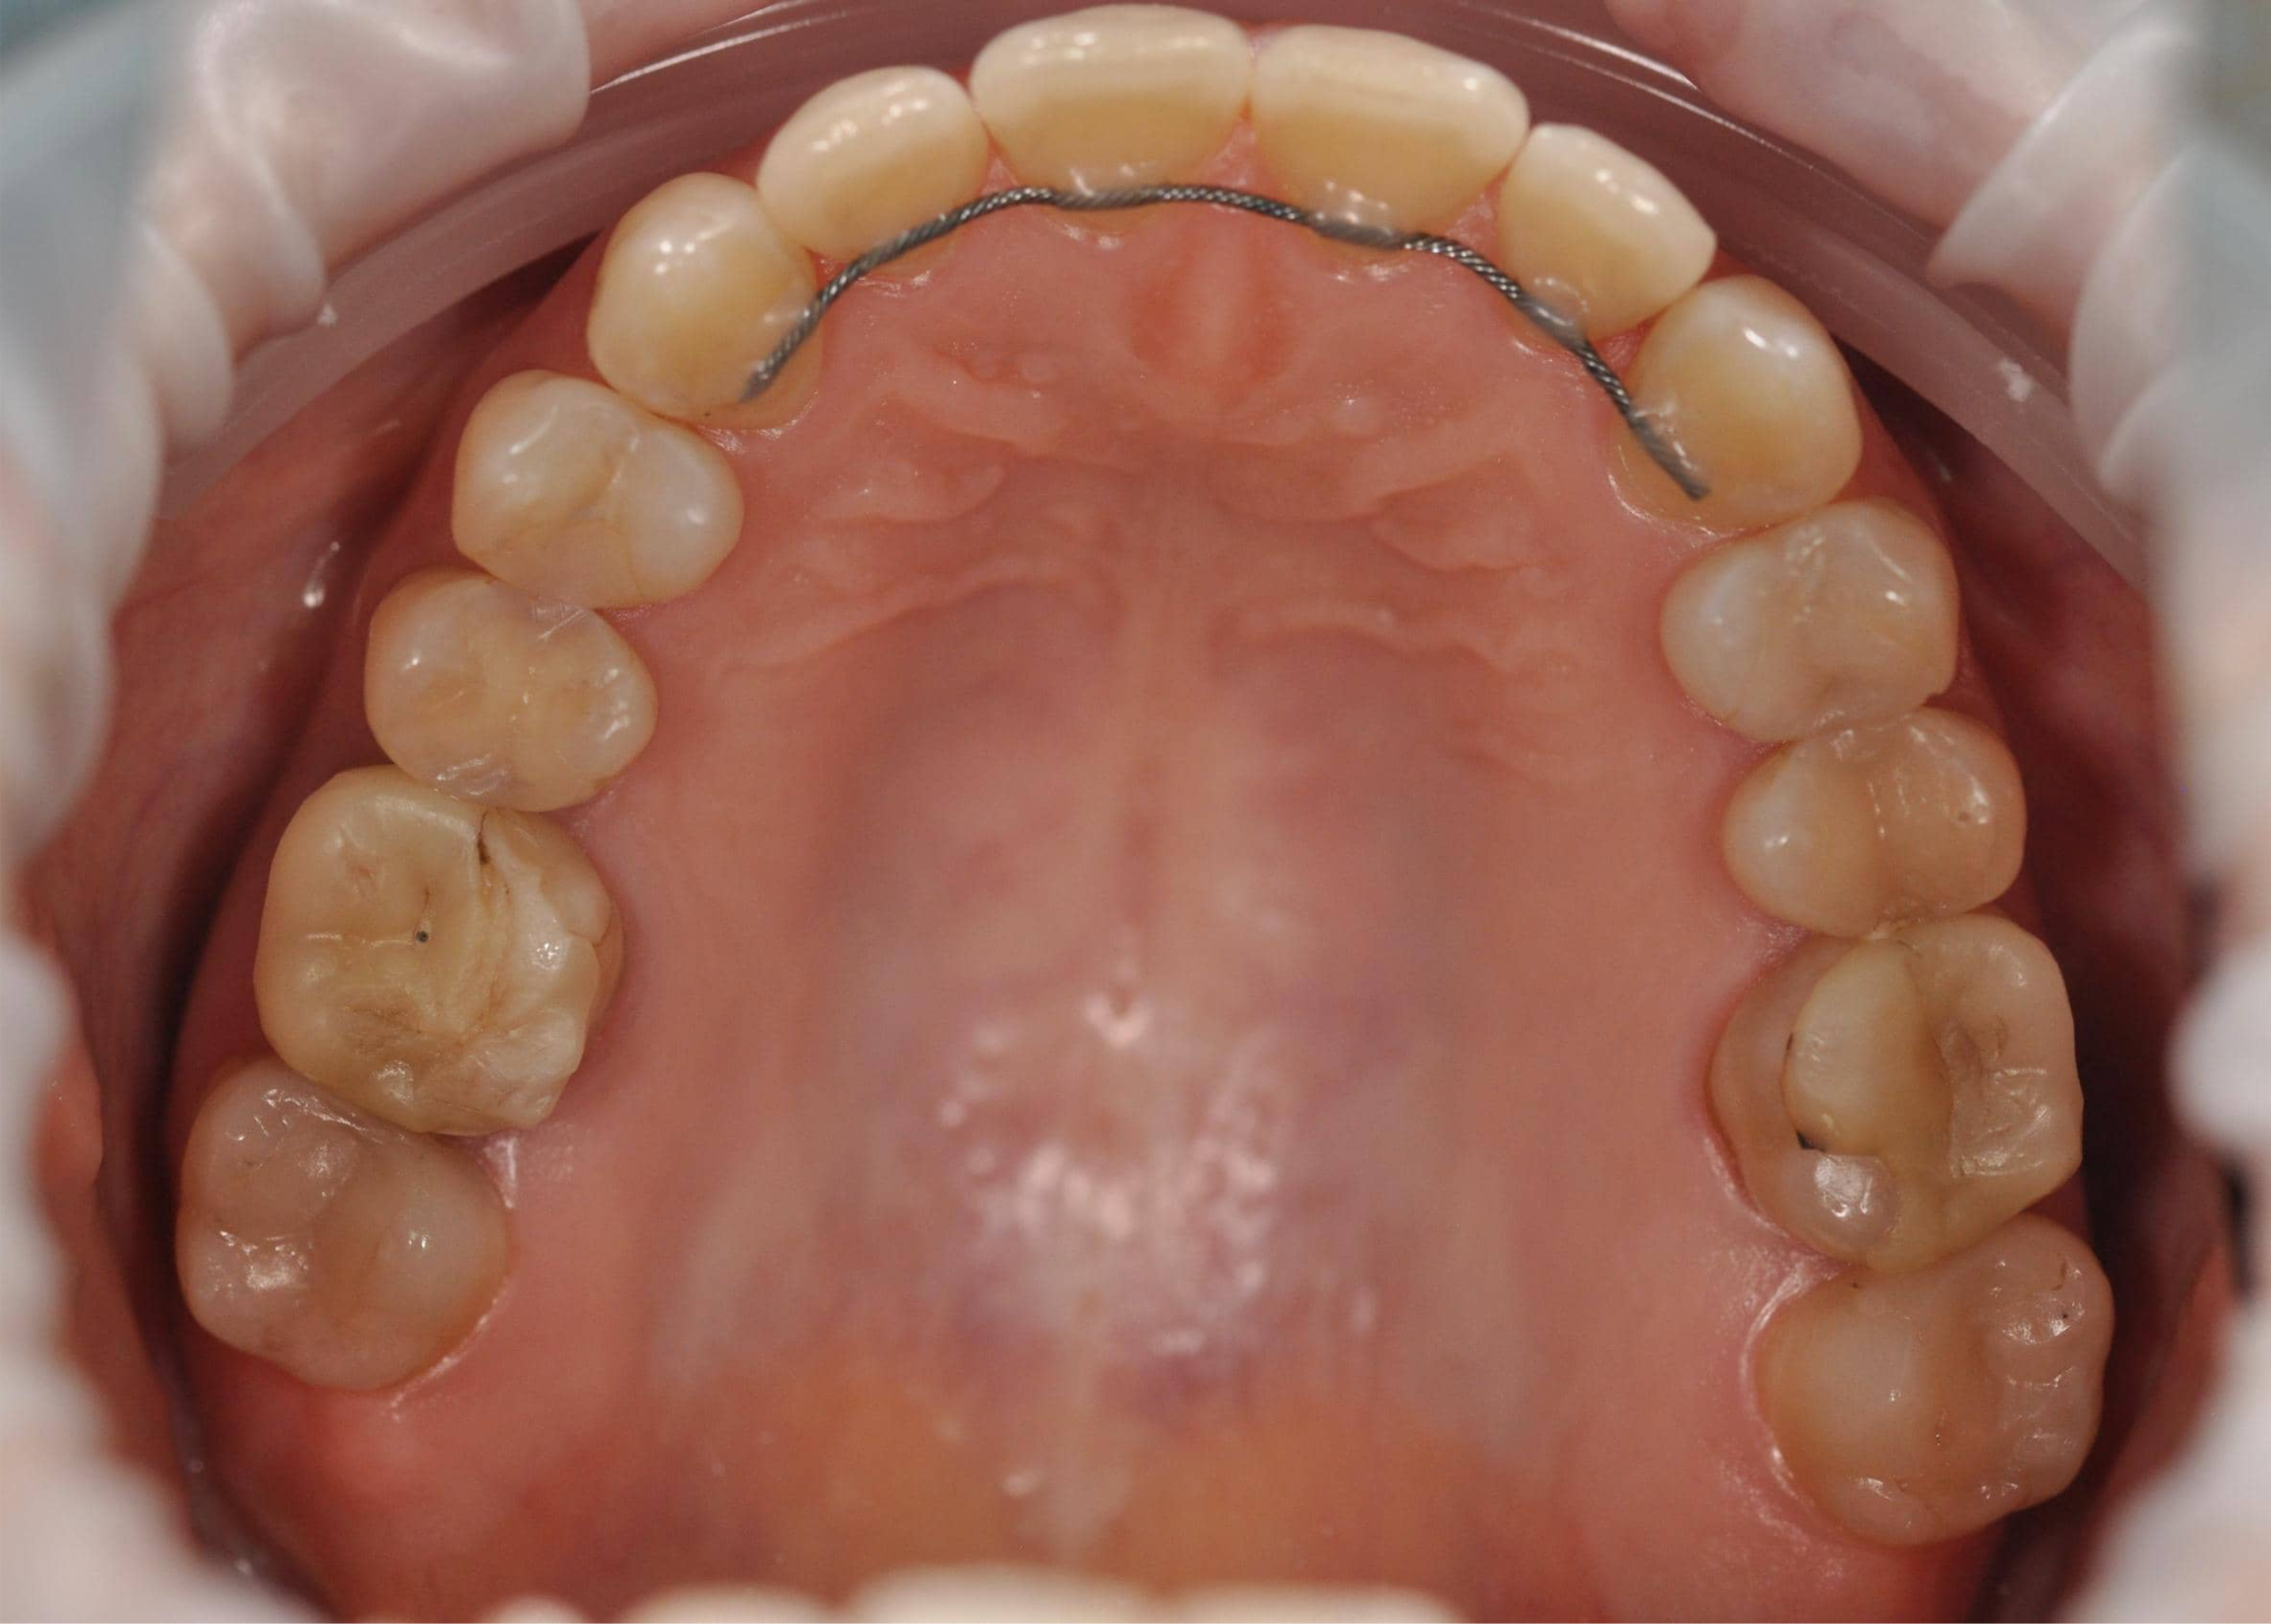

Этап №3

Ортодонтическая коррекция

Стоматолог-ортодонт зафиксировала комбинированную брекет-систему (сверху керамические, а снизу – металлические брекеты).

Ключевые задачи ортодонта:

- Исправление прямого прикуса (одной из частых причин дисфункции ВНЧС).

- Изменение положения зубов.

- Доведение контактов челюстей до физиологически правильного смыкания.

Стоматолог-ортодонт зафиксировал комбинированную брекет-систему (сверху керамические, а снизу – металлические брекеты).